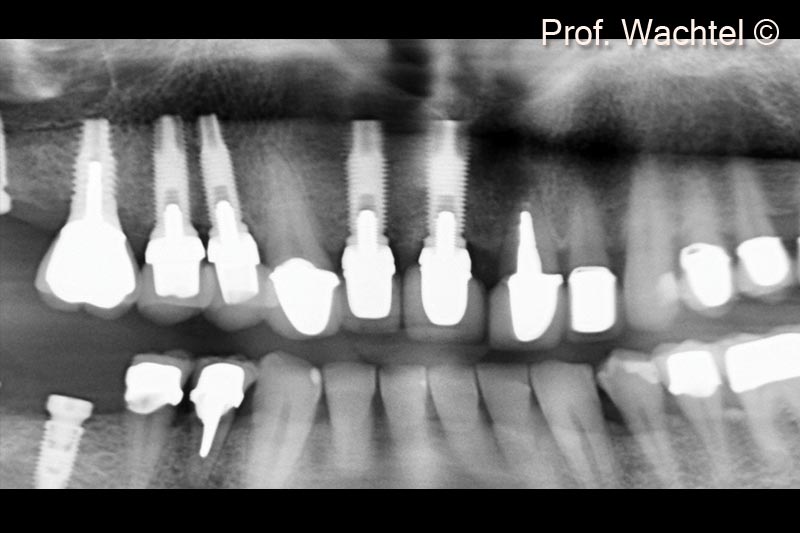

2. Panoramic view before treatment. Tooth #21 is not maintainable due to a large apical lesion